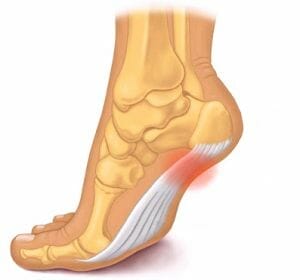

De plantaris is een zeer kleine spier die tussen de gastrocnemius en de soleus ligt. Hij loopt van het lage uiteinde van het dijbeen naar een klein gebied onderaan het hielbeen. De buik van deze spier is ongeveer zeven tot tien centimeter lang en loopt taps toe in een lange, slanke pees die de beide spieren van de kuit kruist en doorloopt naar het hielbeen.

De Plantaris spier strekt de enkel samen met de gastrocnemius als de voet los hangt en buigt de knie als de voet gefixeerd is, bijvoorbeeld tijdens het lopen.